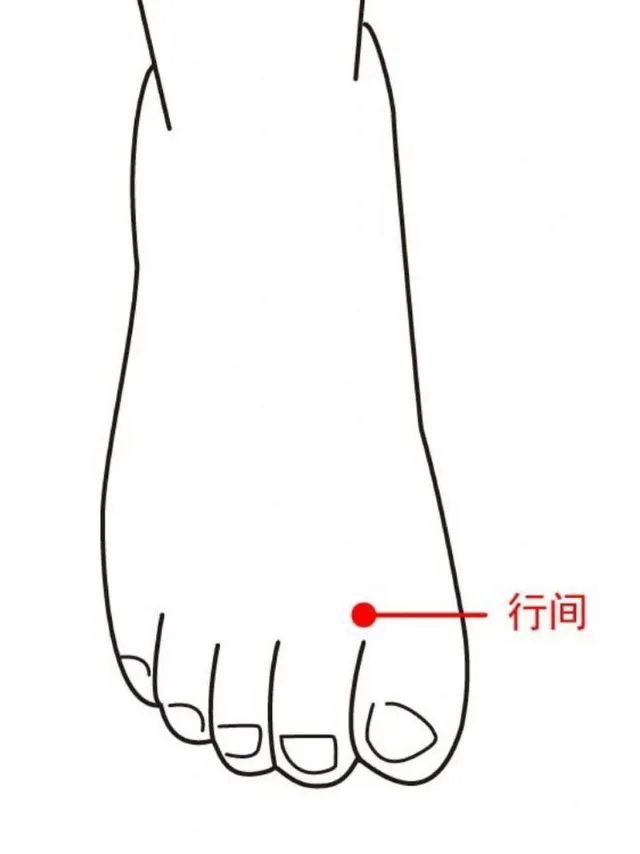

いつものツボ以外に、行間などを追加。肝臓の解毒作業を強化するため。